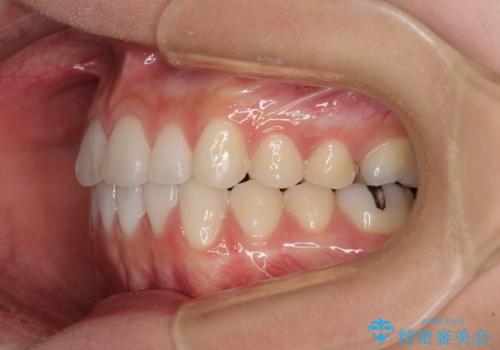

- 上下の八重歯を気にして来院された患者様です。

上下ともに八重歯の後ろの歯を1歯ずつ抜歯し、補助装置(リンガルアーチ)を用いて八重歯の位置を改善し、その後インビザラインにより矯正治療を行うこととしました。

途中海外留学をされたため、治療期間は長くなりましたが、事前に補助装置やワイヤー装置を併用したことで、きれいな歯列に仕上げることができました。